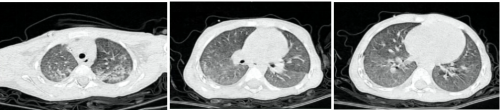

胸部CT检查: